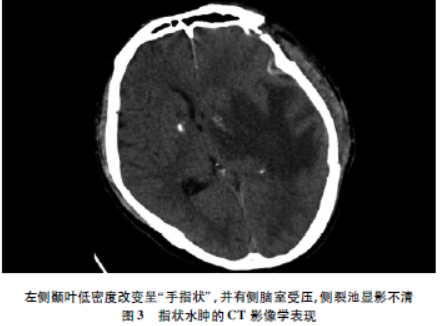

一文掌握各型脑水肿的ct鉴别诊断

图片尺寸640x360